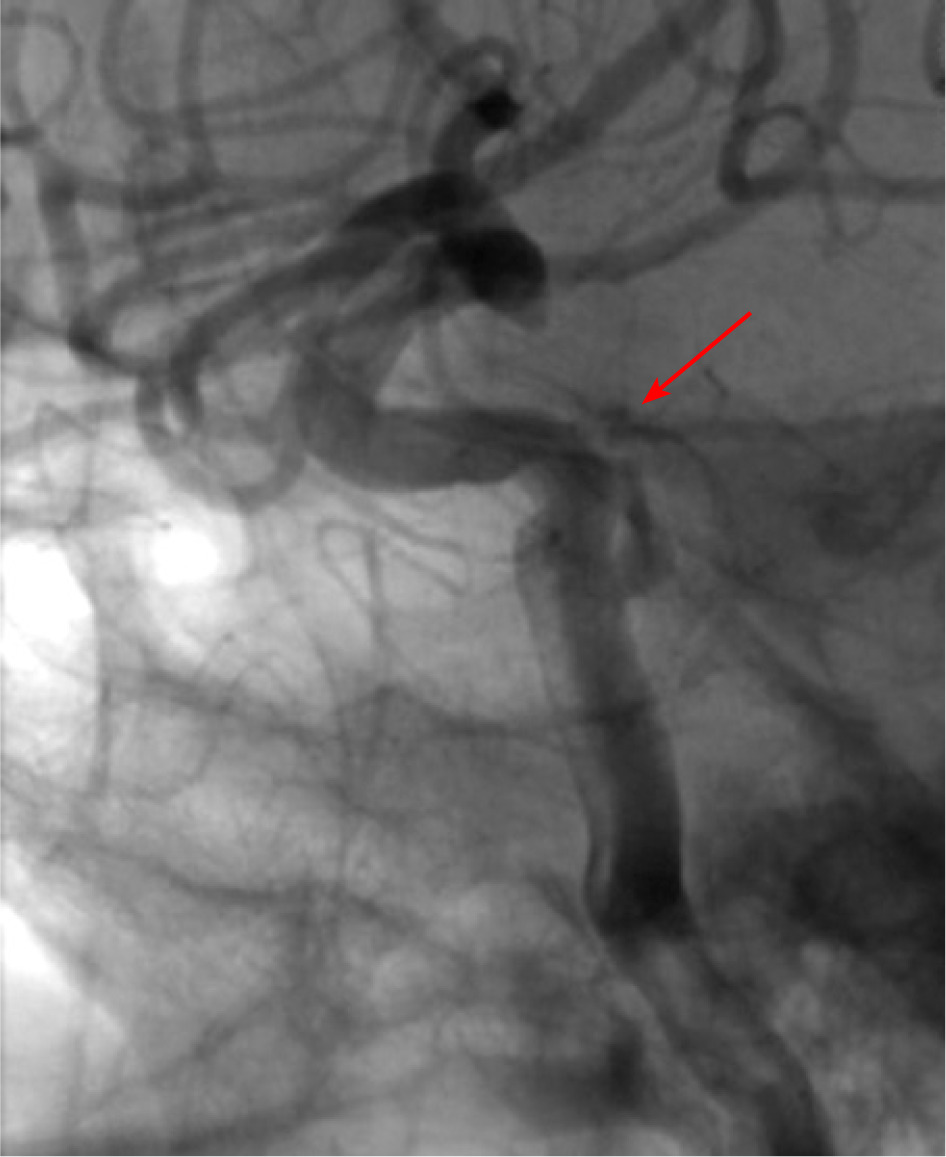

Following the treatment, there was a slight reduction in the patient’s local symptoms, and the IOP in the RE had returned to normal. The patient was transferred to the Department of Neurosurgery for digital subtractive angiography (DSA), which showed a direct carotid-cavernous fistula accompanied by moderate secondary venous dilatation in the right orbit (Figure 7).

Due to deterioration of visual acuity in the RE, secondary glaucoma, and the patient’s subjective symptoms, the decision was made to proceed with fistula embolization. The procedure was performed in the Neurosurgery Department, in a standard manner, without complications. Partial embolization of the fistula was achieved (Figure 8).